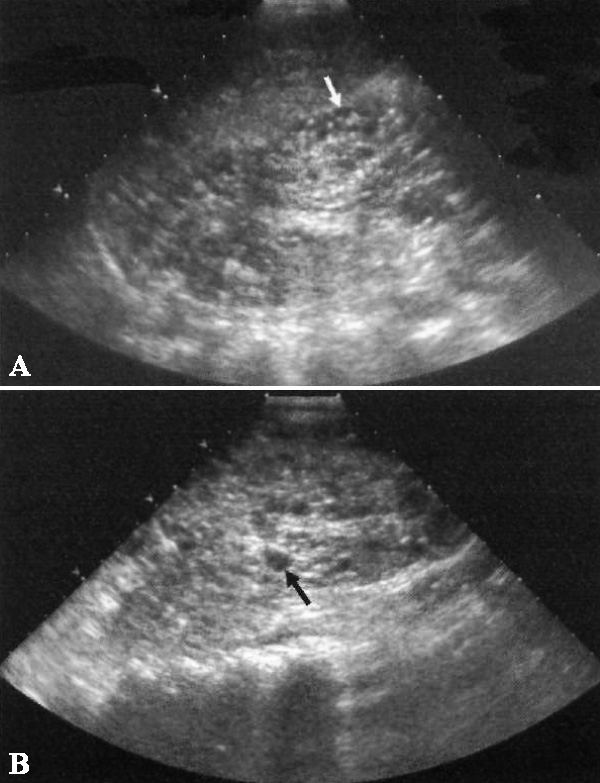

Фото 4. Гидронефроз и уретероцеле. А – продольное ультразвуковое изображение правой почки у ребенка: указателем отмечен выраженный гидронефроз верхней половины удвоенной почки. Также нужно обратить внимание на незначительное выпячивание центрального отдела собирающей системы нижней половины, обусловленное везикоуретеральным рефлюксом (закон Вейгерта-Мейера). В – поперечное ультразвуковое изображение мочевого пузыря того же больного: стрелкой обозначено большое обструктивное уретероцеле, исходящее справа от срединной линии

Если ультразвуковое исследование демонстрирует удвоение собирающей системы с гидронефрозом верхнего полюса, значит в мочевом пузыре нужно искать уретероцеле (фото 4).